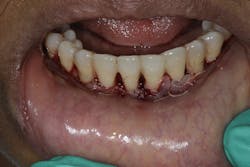

- Follow-up hygiene appointments every three months or less to ensure long-term result (figures 6 and 6a)